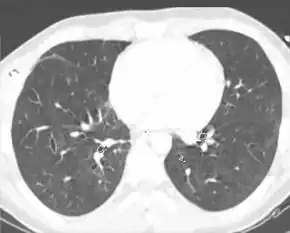

Computed tomography

Computed tomography (CT scanning) is a more sensitive test for pulmonary contusion,[3][32] and it can identify abdominal, chest, or other injuries that accompany the contusion.[37] In one study, chest X-ray detected pulmonary contusions in 16.3% of people with serious blunt trauma, while CT detected them in 31.2% of the same people.[45] Unlike X-ray, CT scanning can detect the contusion almost immediately after the injury.[42] However, in both X-ray and CT a contusion may become more visible over the first 24–48 hours after trauma as bleeding and edema into lung tissues progress.[46] CT scanning also helps determine the size of a contusion, which is useful in determining whether a patient needs mechanical ventilation; a larger volume of contused lung on CT scan is associated with an increased likelihood that ventilation will be needed.[42] CT scans also help differentiate between contusion and pulmonary hematoma, which may be difficult to tell apart otherwise.[47] However, pulmonary contusions that are visible on CT but not chest X-ray are usually not severe enough to affect outcome or treatment.[36]